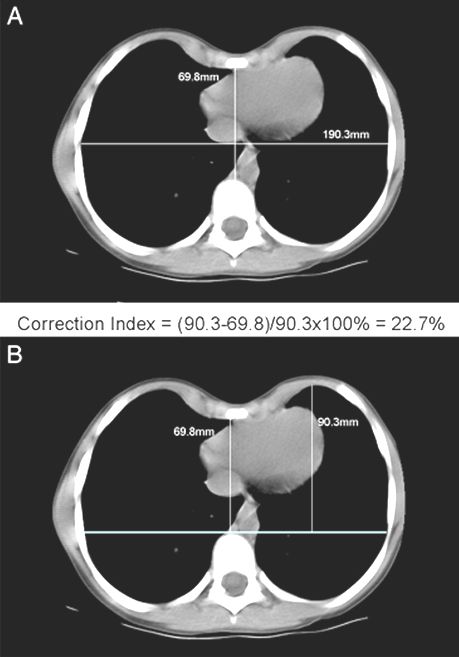

Indice de corrección (IC):  Se miden dos distancias:

1- la distancia mínima entre el esternón y la columna vertebral posterior como se utiliza para el índice de Haller, y

2- la distancia máxima entre la línea trazada por la columna vertebral anterior y el margen interno de la porción más anterior del pecho.

La diferencia entre las dos se divide por la segunda (x 100) para dar el porcentaje de la profundidad del pecho  que representa el defecto.

Ejemplo de la figura: índice de corrección = (90.369.8) / 90.3 X 100% = 22.7%.